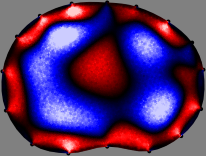

Figs. 3 and 4 compare the performance of the proposed FER method in (20) with the standard regularized least-squares method ((19) when is the identity matrix). The regularization parameter of the standard method was heuristically chosen for its best performance, and the parameter of the FER method was set to be one of three different values . The injection current was 1 mA at 100 kHz, and the frame rate was 9 frames per second. The reference frame at was obtained from the maximum expiration state. The measured data, , represent the voltage differences between each time and . The blue regions, which denote where conductivity decreased by inhaled air, increased during inspiration and decreased during expiration. The FER method with was clearly more robust than the standard method that produced more artifacts originated from the inversion process.

| Standard | |

||||||||||

| FER () | |